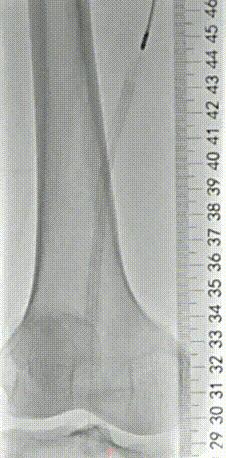

经过周密的术前评估(结合下肢动脉 CTA、ABI 血管功能检测)和多轮讨论后,血管外科姜坤主任团队为李大爷开展微创介入手术,全程在影像引导下精准推进:

▲术前血管造影与CTA相符

▲采用导丝通过支架内闭塞段顺利,考虑为内膜增生合并部分陈旧性血栓病变,再次造影明确病变长度。

▲血管斑块旋切系统逐段旋切抽吸病变段。

▲造影提示治疗效果良好,成功开通闭塞段。

▲Blades Up模式再次抽吸病变段,股腘动脉管腔获得满意,膝下胫后动脉、足部血流灌注同前,未见明显栓塞。

▲股浅、腘、胫后动脉经POBA+5*300 先瑞达DCB球囊扩张。

▲治疗完毕,最终造影结果,股浅动脉局部非限流性夹层,支架内、膝下流出道血流速满意。